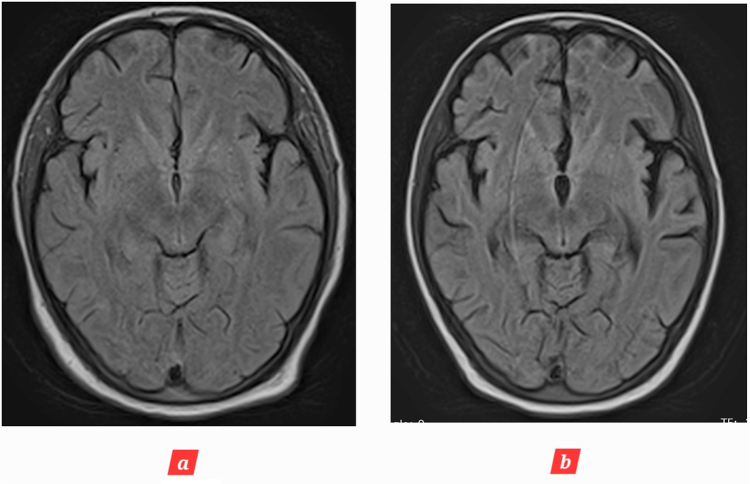

Introduction and importance: Age-inconsistent brain atrophy refers to brain shrinkage that is not proportional to chronological age. This case report is first to report a young patient who developed age-inconsistent brain atrophy due to post cardiac arrest brain injury (PCABI). Due to limitations in the available data, we report our experience and novel magnetic resonance (MR) imaging changes in the brain over the course of 2 months.

Case presentation: We report a case of a 28-year-old woman who developed sudden cardiac arrest during a routine cesarean section, with loss of consciousness for an unspecified period of time. She was resuscitated, intubated and later transferred to intensive care unit (ICU); where her Glasgow Coma Scale on arrival was 4/15. Detailed history, physical examination, and radiological investigations confirmed the diagnosis of PCABI. She was treated in ICU along with physiotherapy for speedy recovery.

Clinical discussion: PCABI is the major cause of long-term disability and mortality following cardiac arrest. In this novel case report, we establish that it can lead to age-inconsistent brain atrophy.

Conclusion: Serial MR imaging scans of the brain should be performed for suspected or confirmed PCABI to evaluate brain atrophy and other changes. This will not only aid in deciphering residual brain deficits but also help in guiding the correct management of the patients.